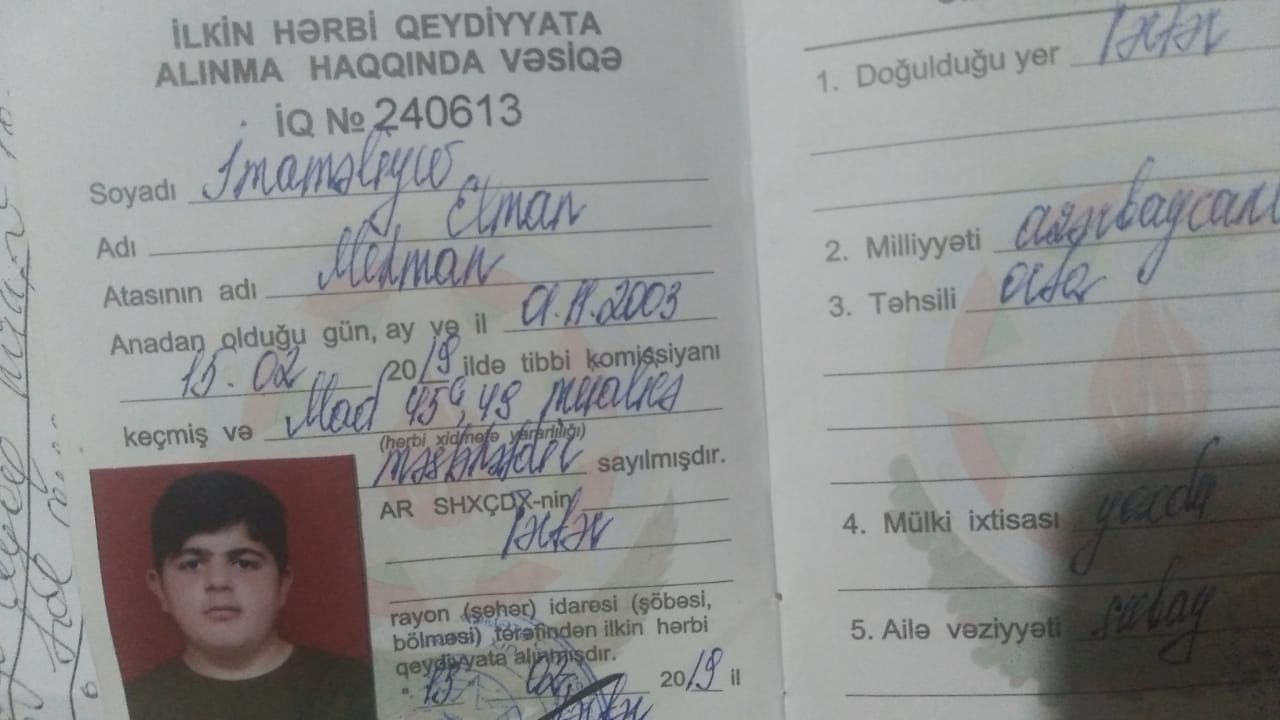

“Oğlum Elman İmaməliyevin ikitərəfli yastıpəncəlik səbəbilə hərbi xidmətə yarasızdır. Bu, Tərtər Rayon Mərkəzi Xəstəxanasından verilən rentgen kağızı ilə təsdiq olunub. Lakin hərbi xidmətə çağırış idarəsinin mayoru oğlumun hərbiyə xidmət üçün yararlı olduğunu əks etdirən saxta sənəd əldə edib. Hansı ki, oğlumun sol ayağı 3-cü, sağ ayağı isə 2-ci dərəcəli ikitərəfli yastıpəncədir.

Hərbi xidmətə çağırış idarəsinin komissiya həkimi rentgen kağızlarını da verib. Amma idarədəki mayor Şahverdiyev uşaqla prinsipə düşdüyü üçün saxta sənəd alıb. O, uşağı təhqir edib, uşaq da deyib ki, səni vuraram. İndi tələb edirəm ki, siz hansı sənədə əsasən müəyyən etmisiz ki, oğlumda hər iki ayağı üçüncü dərəcə yastıpəncədir? Həmin sənədi mənə vermirlər. Deyirlər ki, uşaq yararlıdır, aparırıq. Amma ona verilən möhlət kağızında isə 45-ci və 49-cu maddəyə əsasən, uşağın müalicə almalı olduğu yazılıb”.